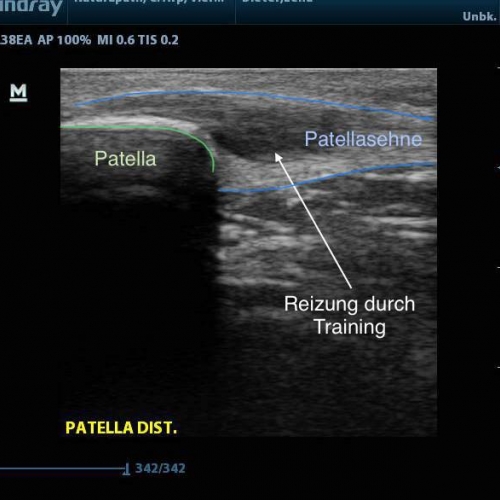

Hierbei werden akustische Wellen (hochfrequente mechanische Schwingungen) durch den Körper geleitet und anschließend von unterschiedlichen Gewebetypen unterschiedlich stark reflektiert. Dies wird dann in ein Bild umgewandelt. Mit entsprechenden Geräten und Wissen lassen sich so viele Diagnosen bestätigen oder ausschließen, angefangen von Muskel- und Bandverletzungen, über Knochenveränderungen bis hin zu Flüssigkeitsansammlungen.

Auch im Rahmen der SPORTMEDIZIN und INJEKTIONSTHERAPIE ist das Sonographiegerät eine tolle Ergänzung. Liegt zum Beispiel ein Muskelfaserriss vor, so kann dieser nicht nur dargestellt und dokumentiert werden, sondern jetzt auch unter Kontrolle ganz gezielt eine Injektion im defekten Bereich gesetzt werden. Auch bei Injektionen an Gelenken wird die Treffsicherheit massiv gesteigert.